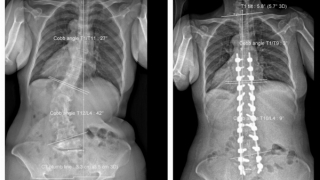

Trả lại 8cm chiều cao cho bệnh nhân sau ca mổ kéo dài hơn 7 giờ đồng hồ

Sáng 24/4, Bệnh viện Trưng Vương TP Hồ Chí Minh cho biết đã thực hiện thành công ca mổ kéo dài hơn 7 tiếng đồng hồ cho một phụ nữ 60 tuổi bị mắc chứng vẹo - còng cột sống, biến dạng cột sống thắt lưng - ngực kèm bệnh lý rễ thần kinh thắt lưng do hẹp ống sống nặng để trả lại 8cm chiều cao cho bệnh nhân…